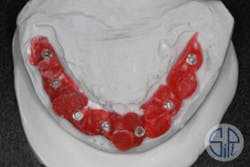

A full-arch restoration on transmucosal abutments was planned. A rigid resin pattern, open-tray, implant level impression was taken (figure 1). The laboratory provided the dentist with straight, transmucosal abutments (figure 2) and a verification jig that was used to verify occlusion, phonetics, and esthetics (figure 3).

Figure 1: Rigid resin pattern, open-tray, implant level impression